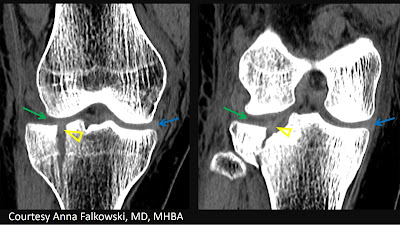

However, preoperative CT revealed an entrapped lateral meniscus (yellow outline) within the fracture.

Note the density of the entrapped lateral meniscus (yellow arrowheads) is equal to the normally located medial meniscus (blue arrows). While the usual meniscal space (green arrows) appears empty or shows lesser density material.

Normal outline of the ACL and PCL. So, the entrapped tissue is not one of those ligaments.